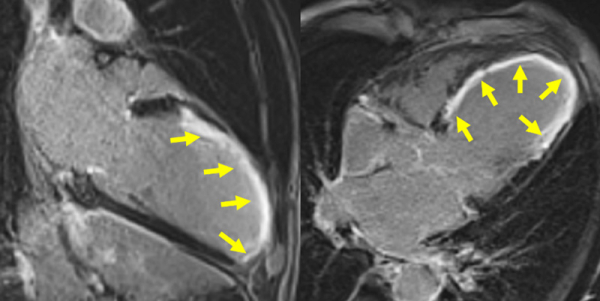

Figure 3A : Séquence de rehaussement tardif - Coupes petit-axe

Figure 3B : Séquence de rehaussement tardif - Coupes long-axe 4 cavités et 2 cavités

Présence d’un large rehaussement tardif sous-endocardique de 8 à 9 segments sur 17 avec un réhaussement transmural (100% de transmuralité) dans la quasi-totalité des segments. Ainsi, si l’IRM cardiaque avait été réalisée à plus de 4 semaines de la phase aiguë nous aurions pu conclure avec certitude à une absence de viabilité.

Cependant, le fait d’être à seulement 2 semaines de la phase aiguë ne nous permet pas de conclure avec certitude à la non-viabilité de cet IDM

Enfin, bien que l’amincissement de la paroi (< 6 mm dans les recommandations en échocardiographie) et l’akinésie soit très en faveur d’une absence de viabilité, plusieurs études ont montré que certains patients pouvaient malgré tout présenter un IDM viable (avec alors un rehaussement tardif < 50% sur l’IRM réalisée à plus de 4 semaines de la phase aiguë).

Aucun thrombus intra-VG n’est visualisé sur ces séquences de rehaussement tardif. Un thrombus serait apparu sous la forme d’une masse en hyposignal (noire) au niveau de l’apex VG par exemple.